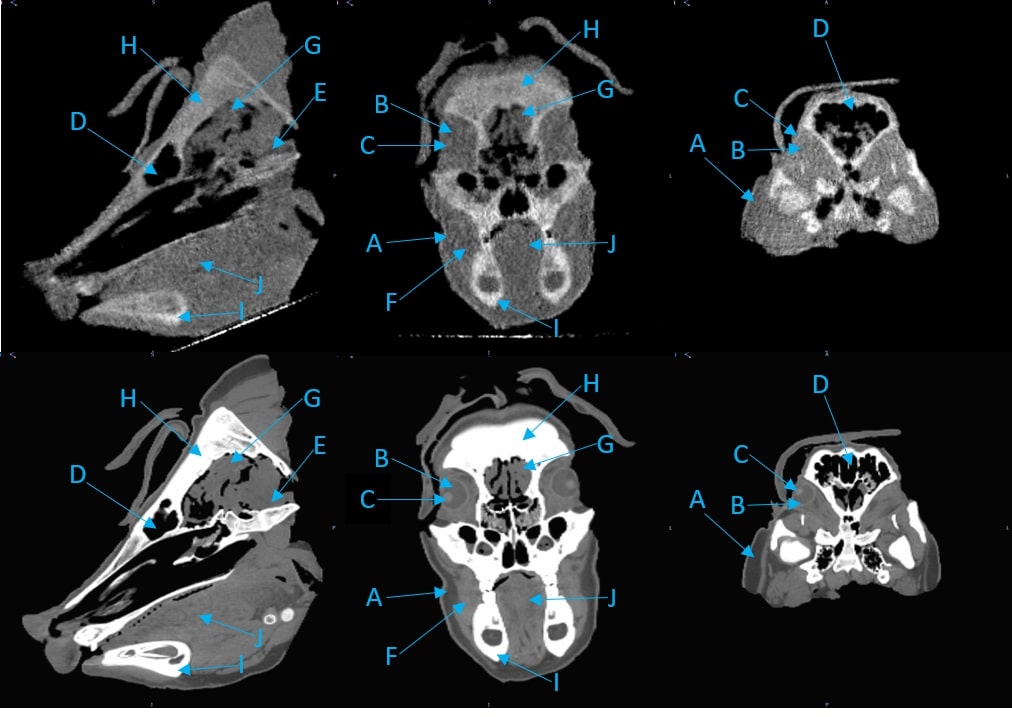

3.D. Comparison of pCT and x-ray CT for the pig’s head

Examples of regions for one slice each in three views of the pig’s head are indicated in Fig. 6, and RSP comparisons between the pCT and the three x-ray CT scans are in Table 3. A close up axial view of the tympanic bullae is shown in Fig 7, which illustrates that the tympanic bullae ROI encompasses a heterogeneous mixture of pneumatized cells separated by thin bony septa. The high and low dose horizontal CT RSPs are consistent within 0.5%. The vertical x-ray CT scan generally shows similar results, although with differences of 2% for brain stem and skull relative to the horizontal scans. Ignoring the RSP differences for sinus air, which are insignificant in absolute terms, the largest difference between pCT and x-ray CT is for the bullae, (-29% to -41%), followed by skull (-2.4% to -4.3%) and brain stem (-2.2% to -4.4%). All other RSP differences (n=24 for 8 tissues) range from -2.5% to +2.1% with a mean of -0.4%. With the exceptions of tongue and lens, the differences for these eight tissues are negative or zero.

Fig. 8 shows a comparison of the average of ten 1 mm sagittal slices from a lateral region of the pig’s head for pCT and the vertical x-ray CT, in order to reduce noise. Features are slightly blurred due to their change in shape with depth. The grey scale reflects the measured RSP, whereas in Fig. 6 and 7 the grey scales were windowed and levelled to optimize contouring. The largest differences are in regions of heterogeneity such as the teeth and tympanic bullae.

The difference map also clearly shows the systematic discrepancy in the skull and the mandible, while soft tissue regions such as brain and muscle regions show closer agreement. The difference in the tip of the snout is caused by an incomplete set of pCT data through that area. The pencil beam scans used for the pCT data set only covered a cm2 area, so the tip of the snout was not quite covered at lateral angles.